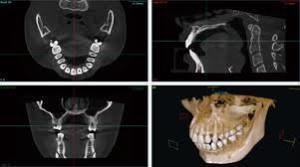

Sコース + CT検査、金属アレルギー検査